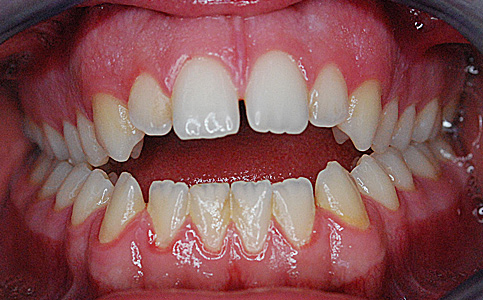

Leczenie ortodontyczne klasy II typ II aparatem stałym DAMON oraz odbudowa estetyczna zębów przednich.

Czas trwania leczenia 2 lata.